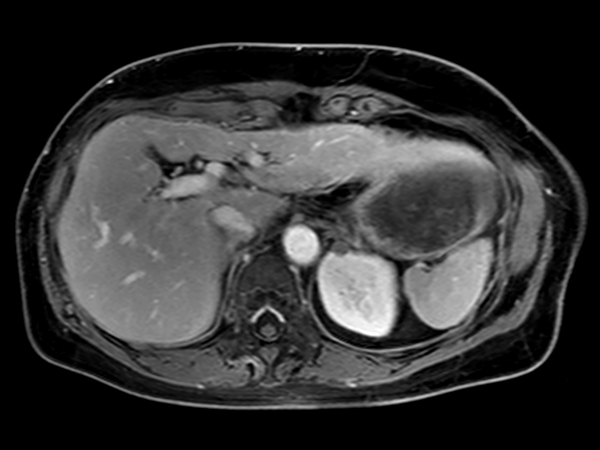

Axial mDIXON – Water (pre-gado) dS SENSE = 6.75, MobiView